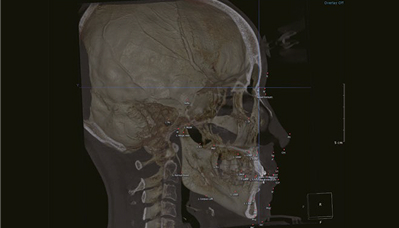

Ортодонтия

3D-анализ позволяет произвести ортодонтический анализ с учётом асимметрии ветвей НЧ и других анатомических образований черепа человека.